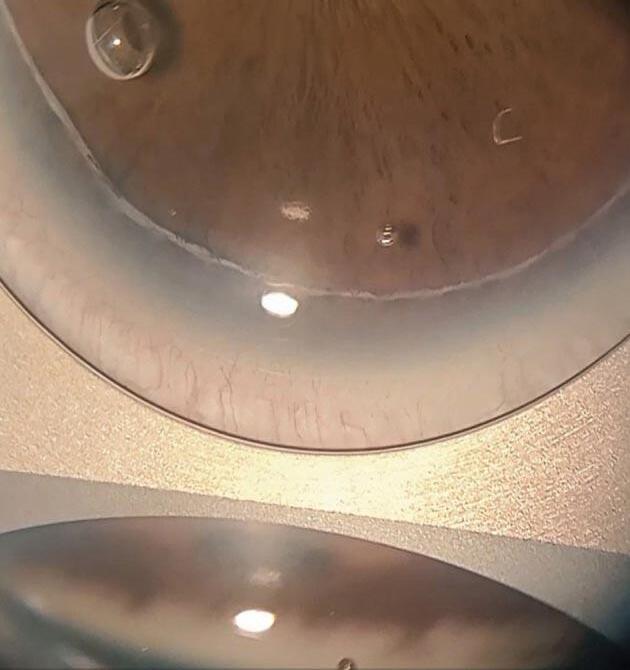

Figura 1. Embriotoxon posterior OD. Figura 2. Embriotoxon posterior OI. Figura 3. Embriotoxon posterior a la gonioscopía. Figura 4. Goniodisgenesias adheridas a embriotoxon posterior por gonioscopía.

Se presenta a la consulta una paciente femenina de 18 años a control oftalmológico de primera vez, sin antecedentes personales, familiares ni oftalmológicos de relevancia, con una AV mejor corregida 20/20 ambos ojos, con un exámen a la lámpara de hendidura cuyos datos positivos fueron embriotoxon posterior bilateral ( Línea de Schwalbe anteriorizada y prominente), y goniodisgenesias en los 360° que se confirmaron bajo estudio gonioscópico con lupa de cuatro espejos de Goldmann.